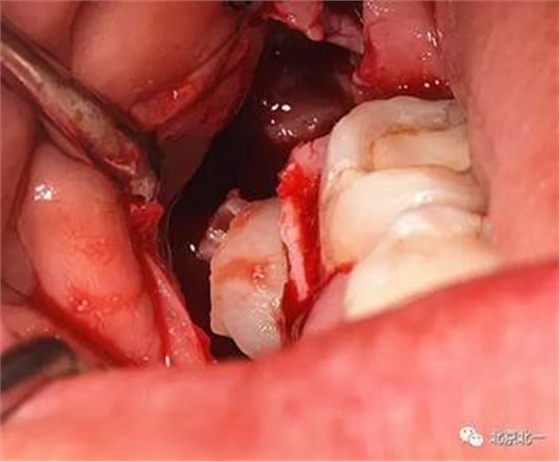

圖六:切開翻瓣, 看見骨面清晰,未見智齒

圖七:去骨后看不見牙齒位置方向。顏色無法區(qū)分,拍片確認一下剛才去骨的以及截的冠就是智齒。

圖八:把牙根優(yōu)先取出后還是看不見牙冠在哪里,實在貼的神經管太近, 只能再次拍一個cbct確認。

圖九:重建后可見牙冠位于第二磨牙遠中,舌側傾斜。

圖十:實際情況:看到么在第二磨牙頰側接近近中區(qū)域。關鍵牙顏色和骨顏色一致, 只有牙冠部分是白色能看出來, 但是它卻深深的把頭埋下。